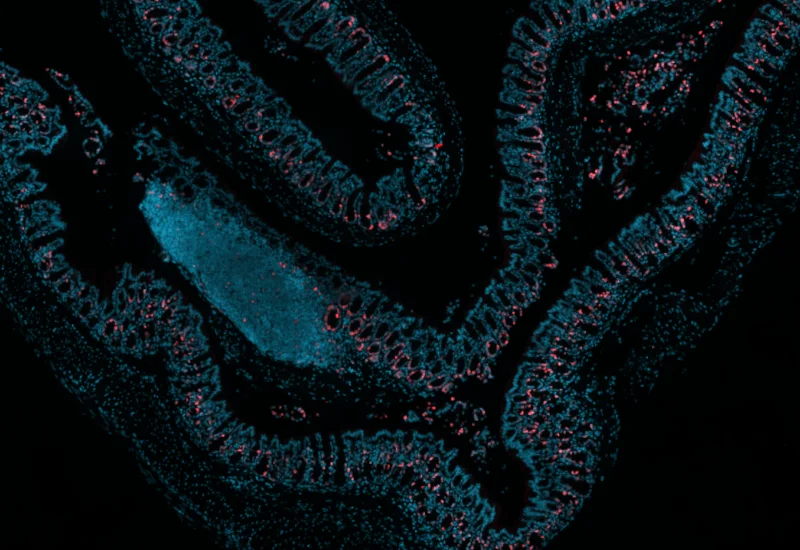

mouse, colon, fluorescence, immune cell follicles

Original Image